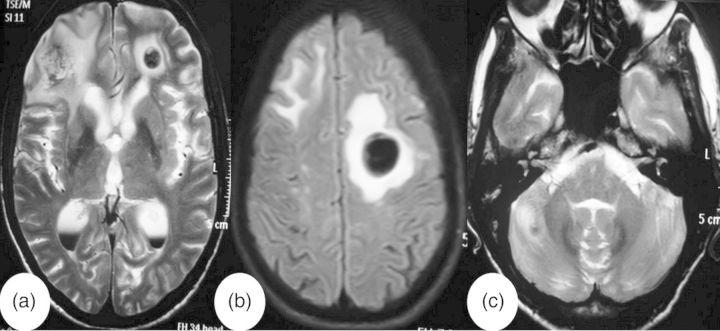

Longitudinally extensive transverse myelitis (LETM) is an unusual manifestation of systemic malignancy. It has been mainly reported with lung cancers and lymphoproliferative malignancy. LETM in systemic malignancy can be caused by either intramedullary metastases or paraneoplastic syndrome. We report an unusual case of small-cell carcinoma lung, who presented with LETM without having any cardinal manifestations of lung malignancy. This case report highlights the important differentiating features between intramedullary metastasis and paraneoplastic syndrome.

长节段横贯性脊髓炎(LETM)是系统性恶性肿瘤的一种罕见表现。主要报道与肺癌和淋巴增殖性恶性肿瘤有关。系统性恶性肿瘤中的LETM可由髓内转移或副肿瘤综合征引起。我们报告一例罕见的小细胞肺癌病例,该患者表现为LETM,但无任何肺癌的主要表现。本病例报告强调了髓内转移和副肿瘤综合征之间重要的鉴别特征。